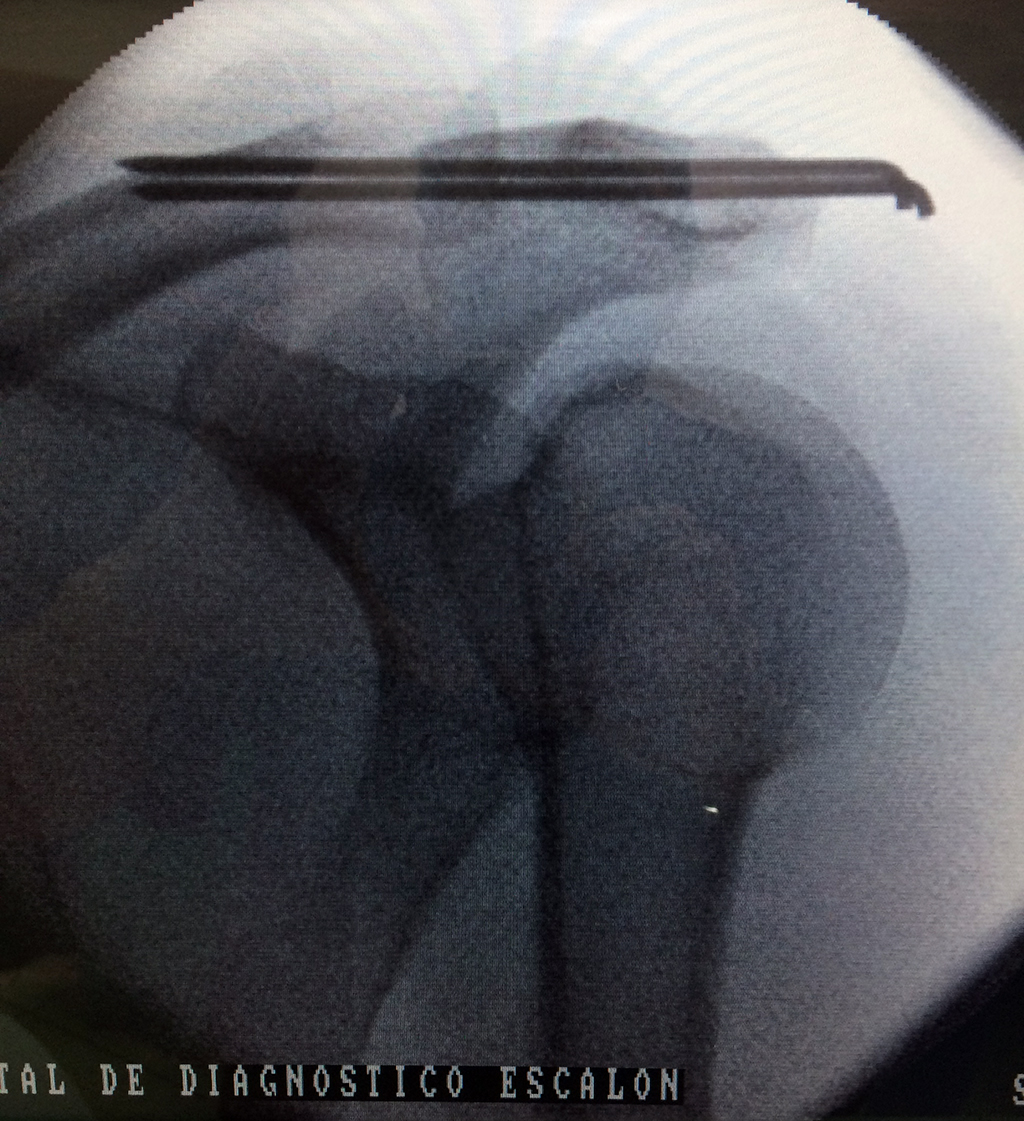

Cirugías de Húmero - Clavícula